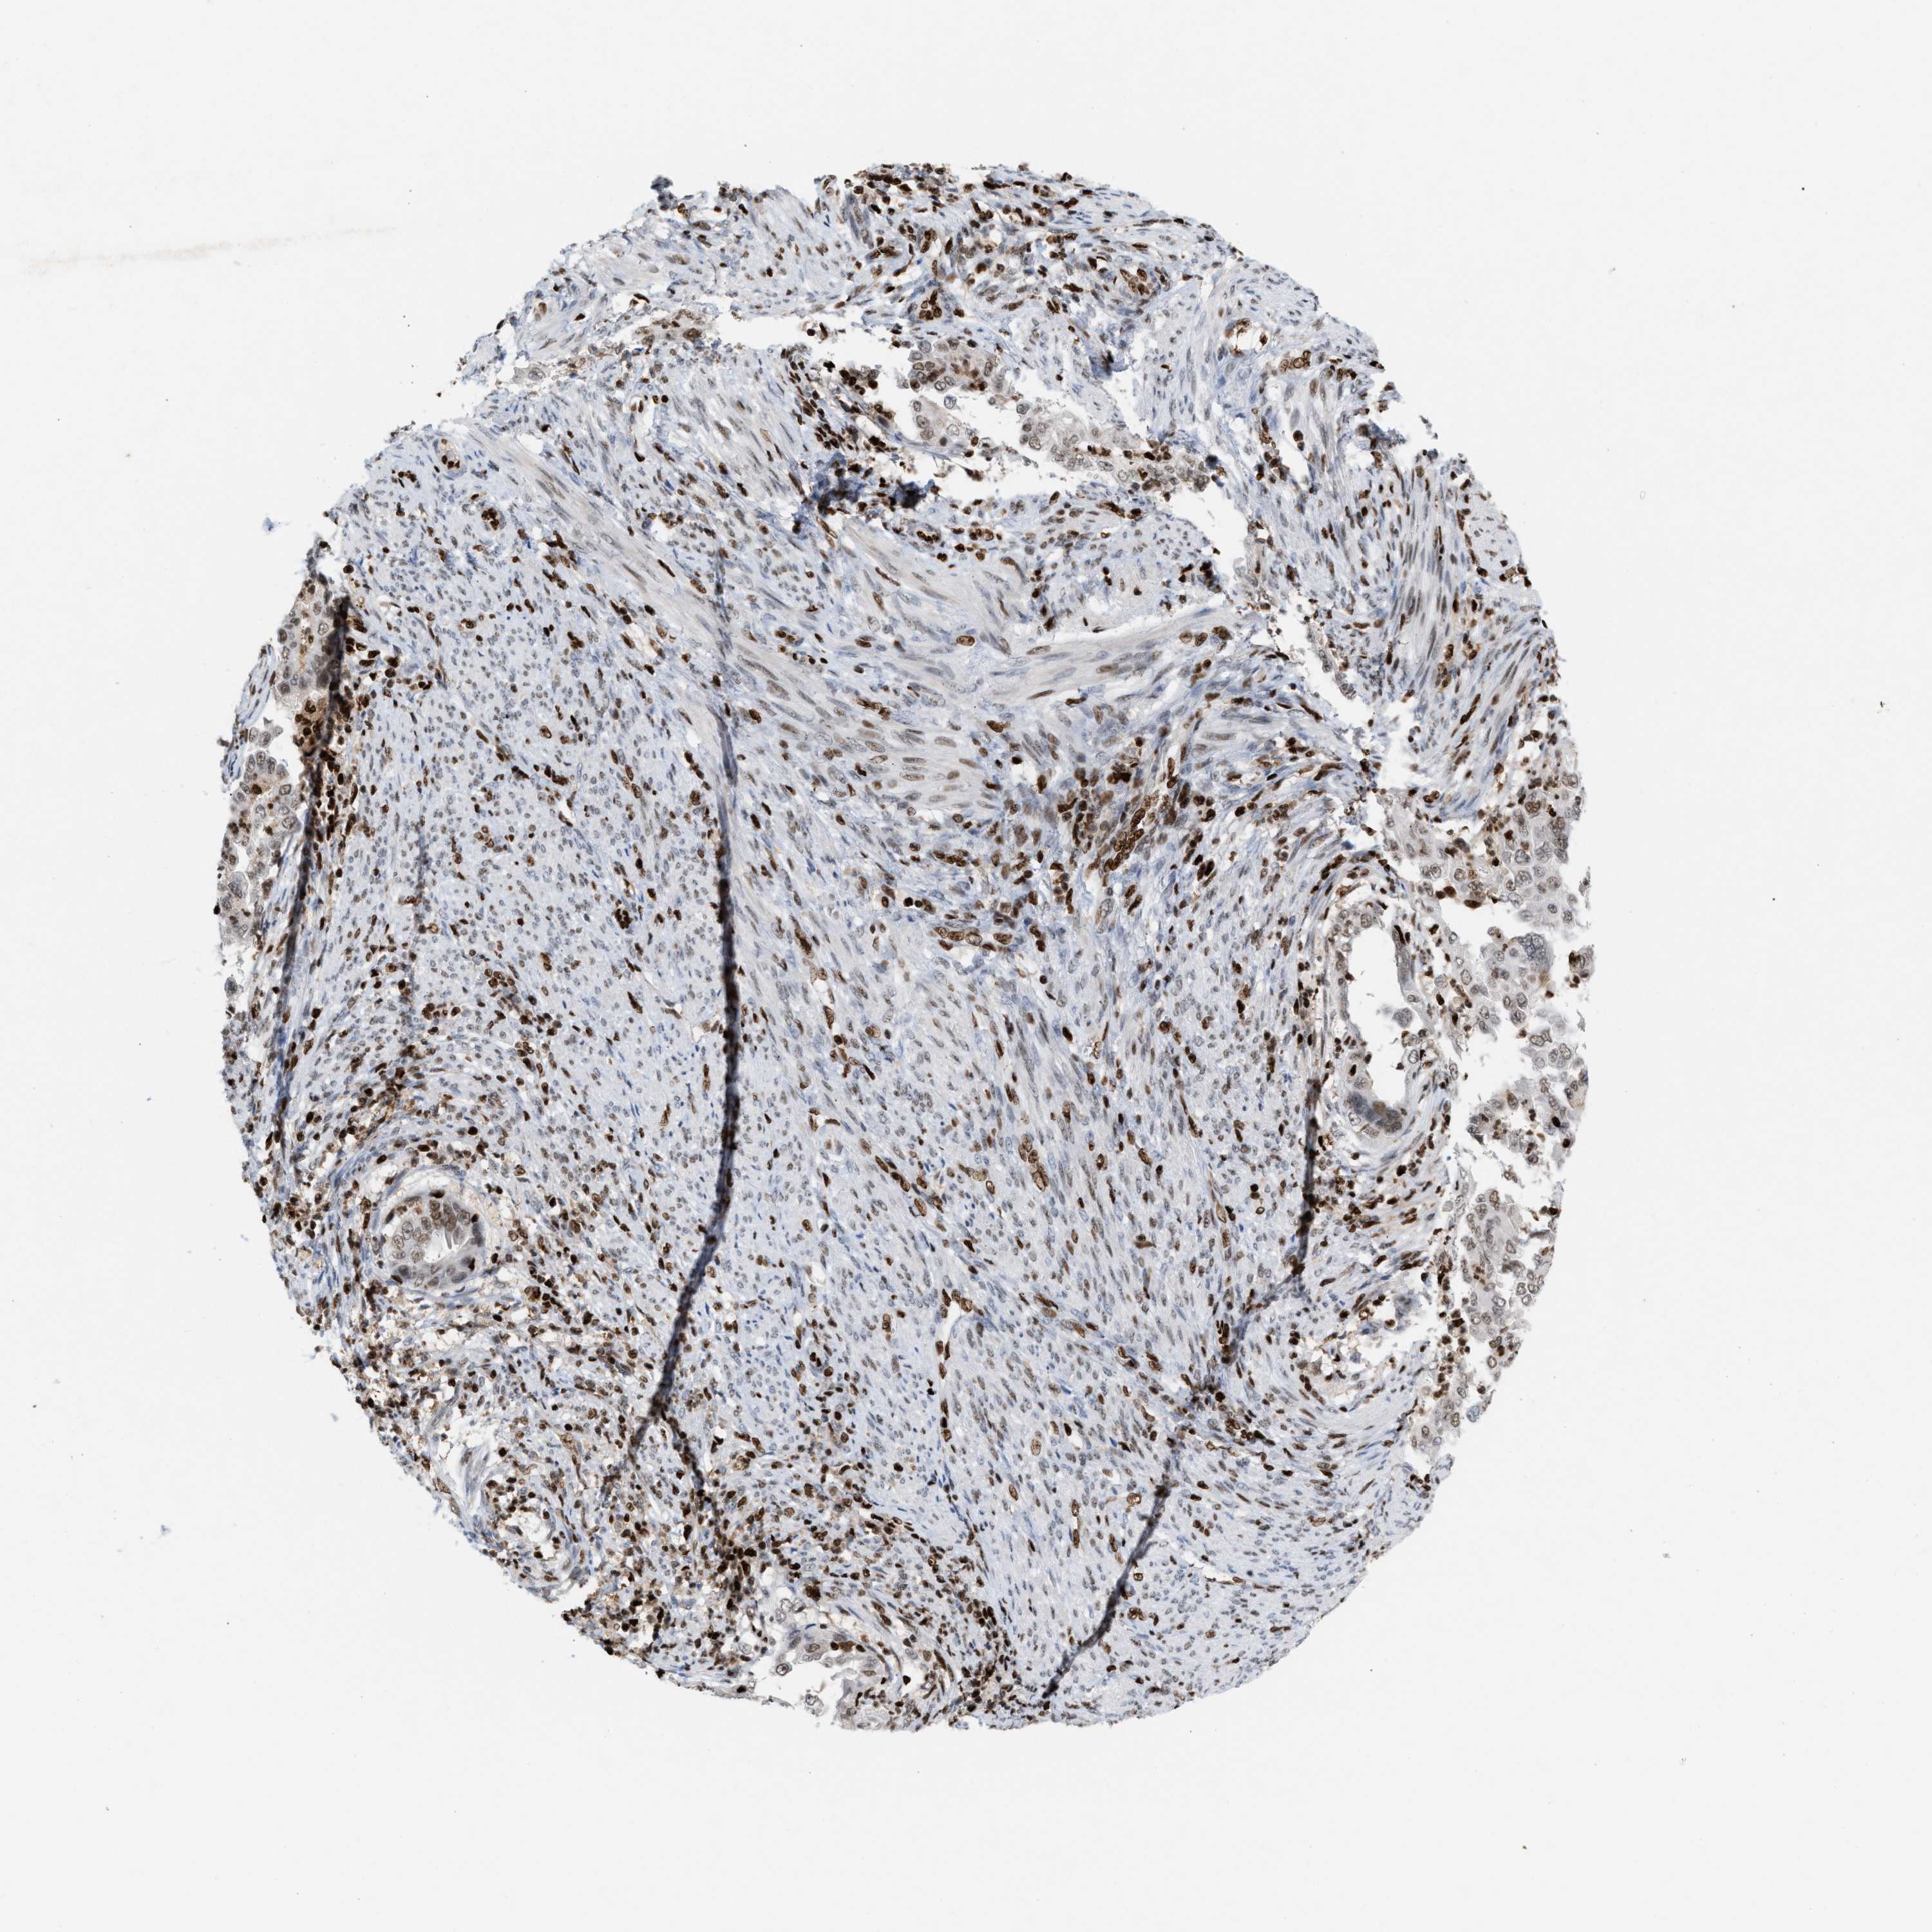

ENDOMETRIAL CANCER - Protein expressioni

A mouse-over function shows sample information and annotation data. Click on an image to view it in a full screen mode. Samples can be filtered based on level of antibody staining by selecting one or several of the following categories: high, medium, low and not detected. The assay and annotation is described here.

Note that samples used for immunohistochemistry by the Human Protein Atlas do not correspond to samples in the TCGA dataset.

Antibody stainingi

Antibody staining in the annotated cell types in the current human tissue is reported as not detected, low, medium, or high, based on conventional immunohistochemistry profiling in selected tissues. This score is based on the combination of the staining intensity and fraction of stained cells.

Each image is clickable and will lead to virtual microscopy that enables deeper exploration of all samples and also displays staining intensity scores, fraction scores and subcellular localization as well as patient and tissue information for each sample.

Antibody HPA022961

Antibody HPA024457

Staining

High

Medium

Low

Not detected

Intensity

Strong

Moderate

Weak

Negative

Quantity

>75%

75%-25%

<25%

None

Location

Nuclear

Cytoplasmic/membranous

Cytoplasmic/membranous,nuclear

Adenocarcinoma, NOS